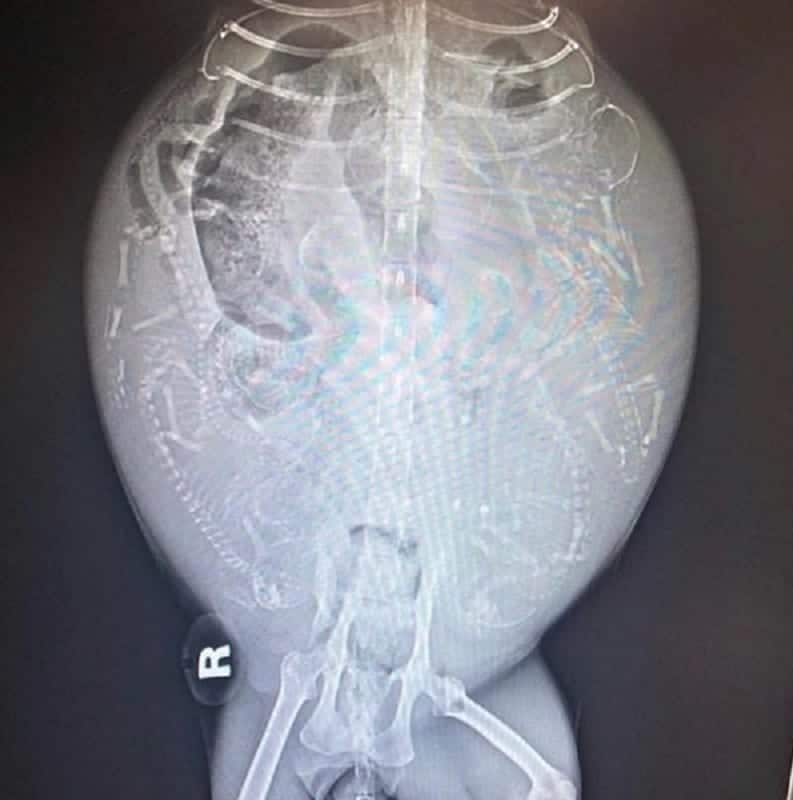

Slowly, Dot began to heal. Two months later, x-rays showed her pelvis was repairing itself.

Dot was pregnant, and not with a small litter.

She was carrying ten kittens.

Her age and previous injuries made the pregnancy incredibly risky.